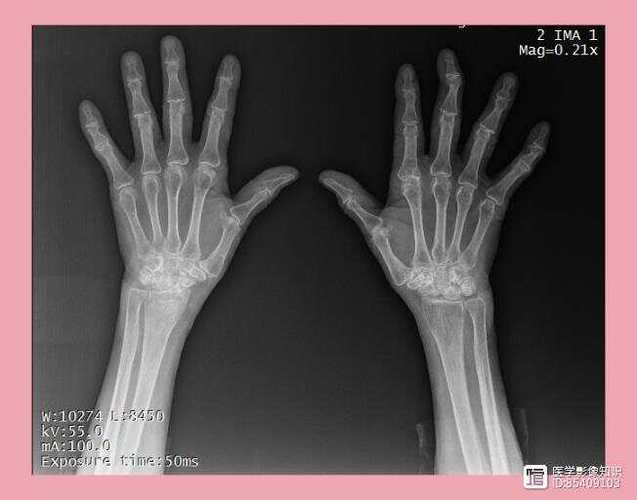

X线检查

- 作用: 是评估RA骨侵蚀性破坏的传统“金标准”。

- 典型表现:

- 关节周围骨质疏松: 最早期的表现。

- 关节间隙狭窄: 由于软骨破坏所致。

- 骨侵蚀: 边缘性、虫蚀样骨质破坏,是RA的特征性改变。

- 关节畸形: 如尺侧偏斜、天鹅颈样畸形、纽扣花畸形等晚期改变。

- 局限性: X线对早期软骨和轻微骨侵蚀不敏感,通常在发病数月后才出现明显改变。